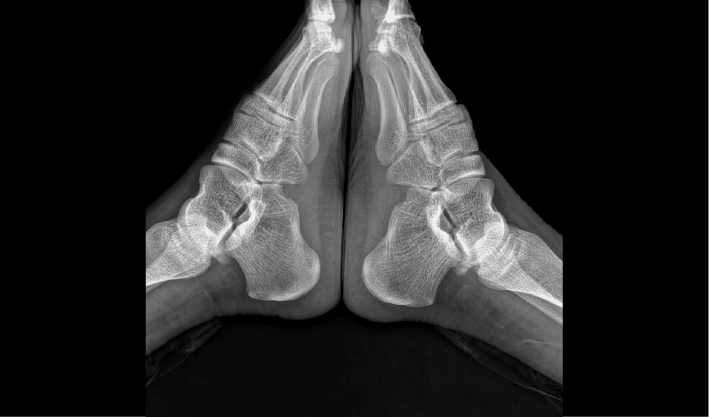

配合十軸智能全自動操控,實現六向跟蹤和一鍵自動擺位切換,融合高端配置,帶來一流的圖像,簡便操控,快捷流程,輔助醫生快速精準診斷。

消除線噪聲的同時不損失圖像細節,保持邊緣和分辨率,不會引入新偽影,增加圖像銳利度。

管球無位移,消除運動誤差,提高拼接成功率。

重疊區域面積小,減少曝光次數,減少輻射劑量。

AEC自動曝光和影像均衡算法,保證拼接圖像統一亮度和對比度。